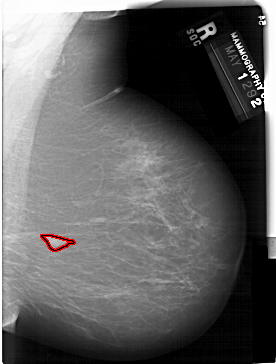

A_1128_1.RIGHT_CC

FILE: A_1128_1.RIGHT_CC.OVERLAY

TOTAL_ABNORMALITIES 1

ABNORMALITY 1

LESION_TYPE MASS SHAPE LOBULATED MARGINS MICROLOBULATED

ASSESSMENT 4

SUBTLETY 5

PATHOLOGY MALIGNANT

TOTAL_OUTLINES 1

BOUNDARY